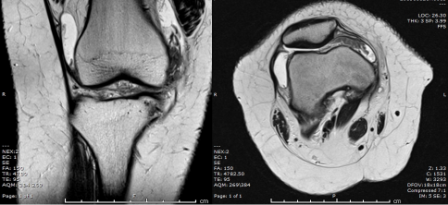

MRI of the knee was performed.

Q. What is your opinion on the MRI scan?

Knee joint effusion

Hypertrophy of the synovium

Normal cartilage and bony outline. Meniscus, ACL, and PCL were intact.

MRI is the best approach showing the masslike synovial proliferation with lobulated margins, with low signal intensity and "blooming" artifact on gradient echo due to haemosiderin deposition [4].